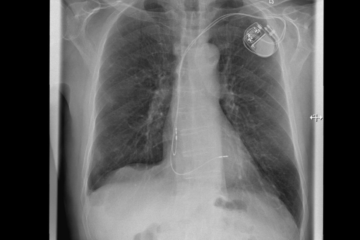

Kardiologie: Fakten zur minimalinvasiven Herzklappenintervention

Wie lassen sich Undichtigkeiten der Herzklappen behandeln – Informationen aus Siegen SIEGEN. Verschiedene Erkrankungen des Herzens oder der Lunge können…